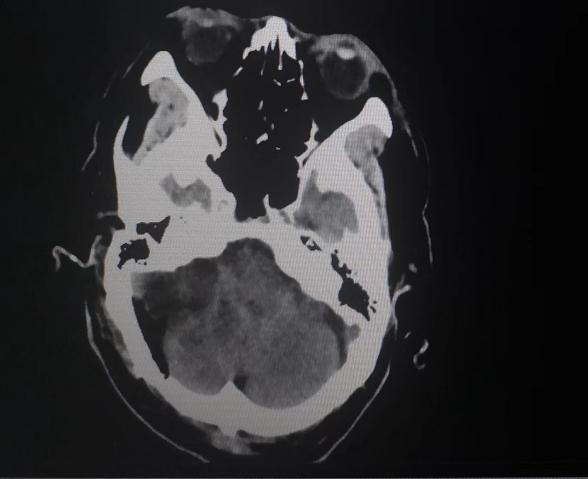

患者入院后,头颅MR检查后发现,小脑右侧长了巨大肿瘤,直径约6公分,患者家属收到不小的惊吓。患者4年前曾做过一次头颅核磁共振,当时肿瘤较小,考虑到患者已经88岁,家人还是决定保守观察,没想到如今,它已经长大到足足有一个土豆那么大,而且患者头晕较重,反复恶心、呕吐,卧床不起,因此必须进行手术,才能解决患者病症。